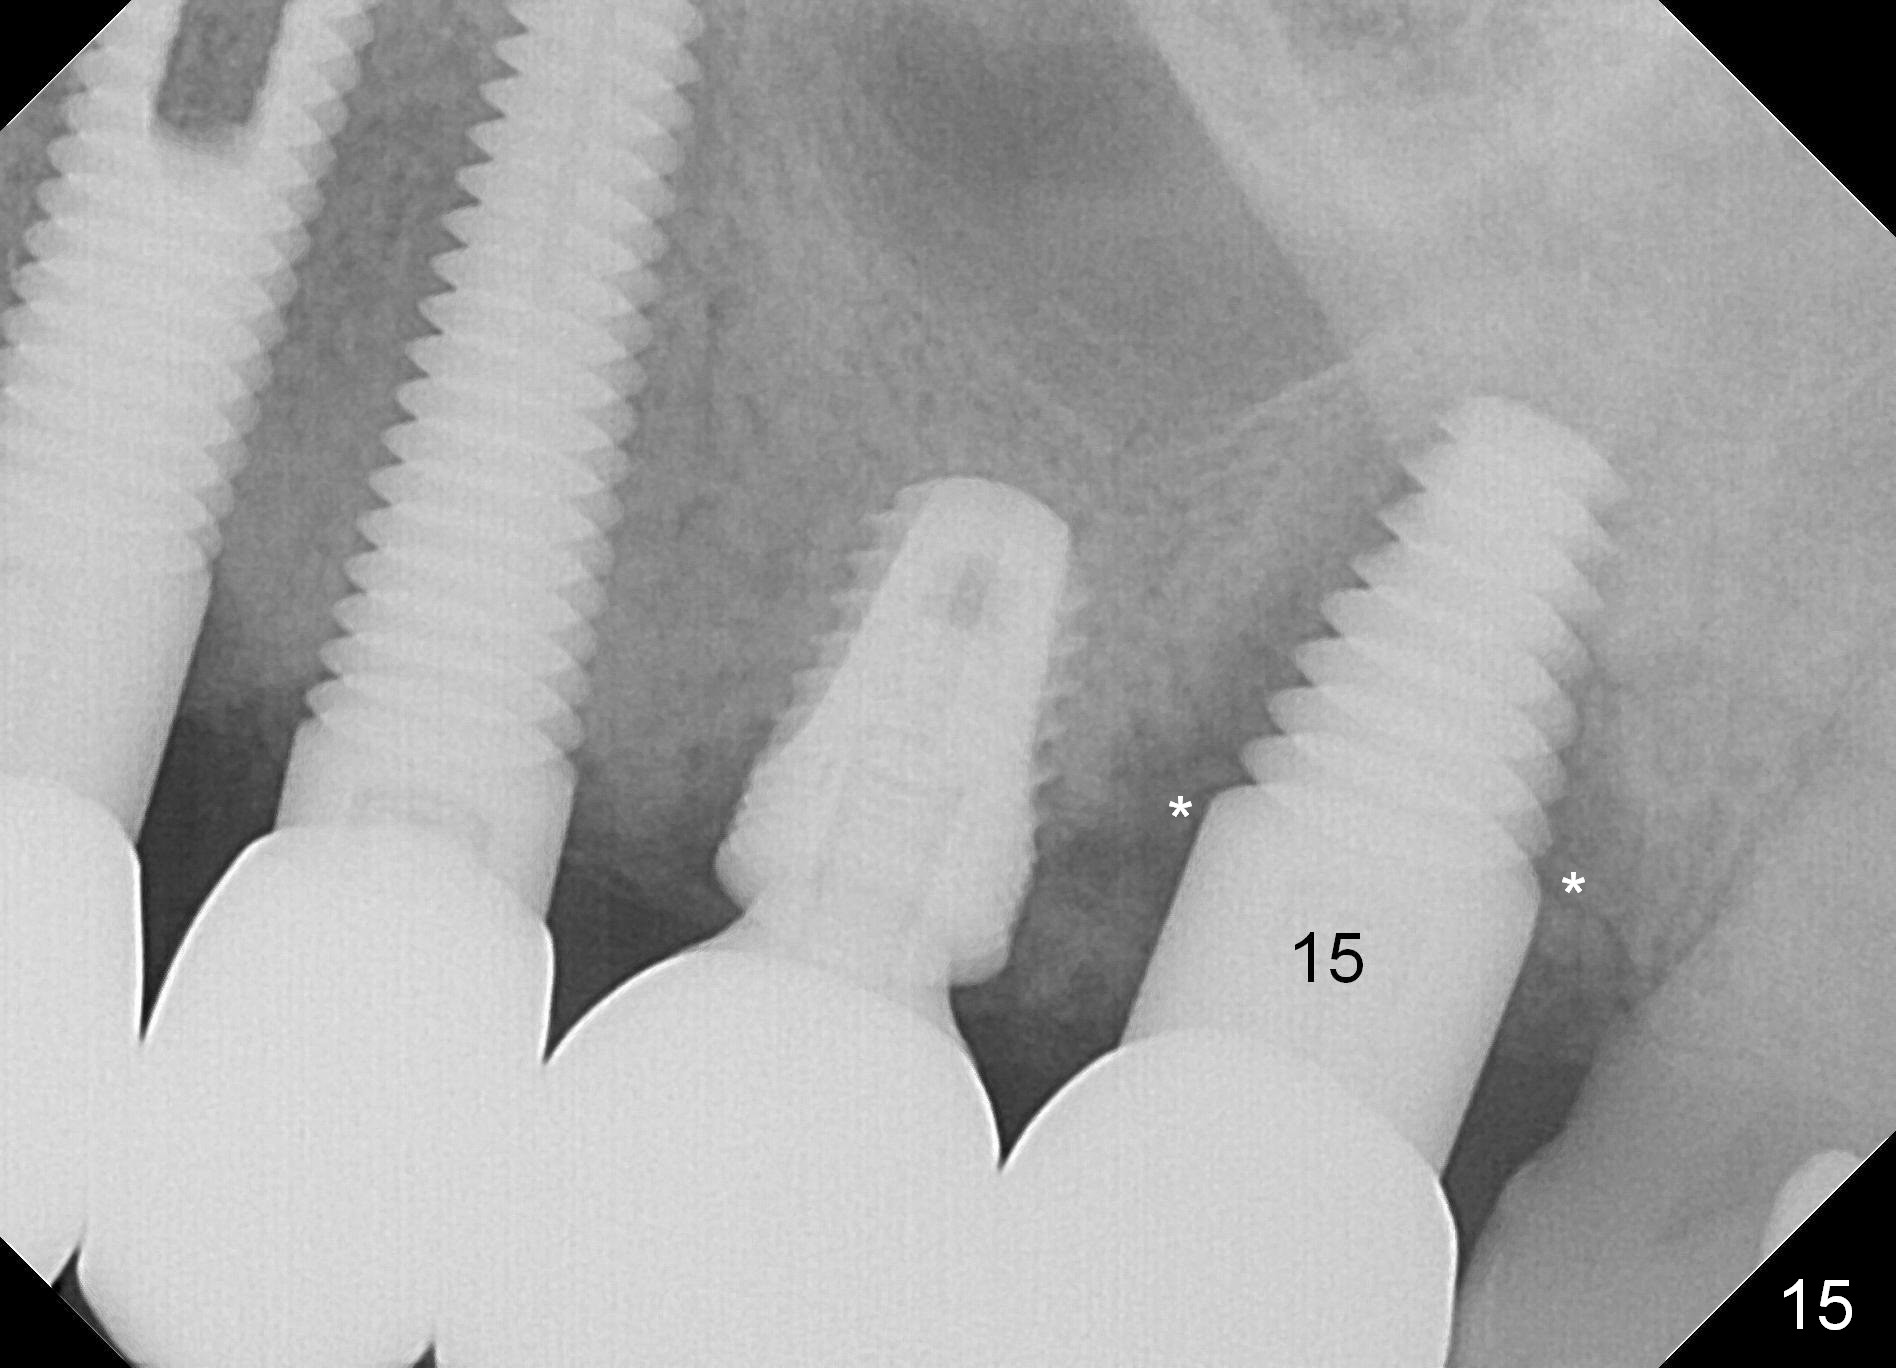

The implant crown at #15 becomes loose with pain and radiolucency around the implant (Fig.15 *) 2 years 2 months post cementation.  The implant is removed without difficulty.  The site is closed with Osteogen plug.  Next visit use RTs 2-4 to extend the osteotomy for 3-6 mm, followed by tapered taps.  If stability is low, change to cylindrical taps.  Place a 6x20 or 7x17 or 20 mm implant.